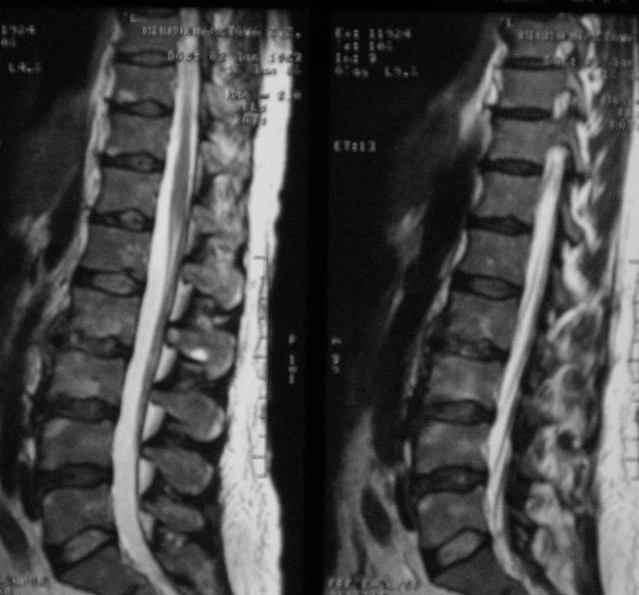

Отправляю MRI в динамике, снятые с пленки на фотоаппарат.

Имя     : при госпитализации.jpg